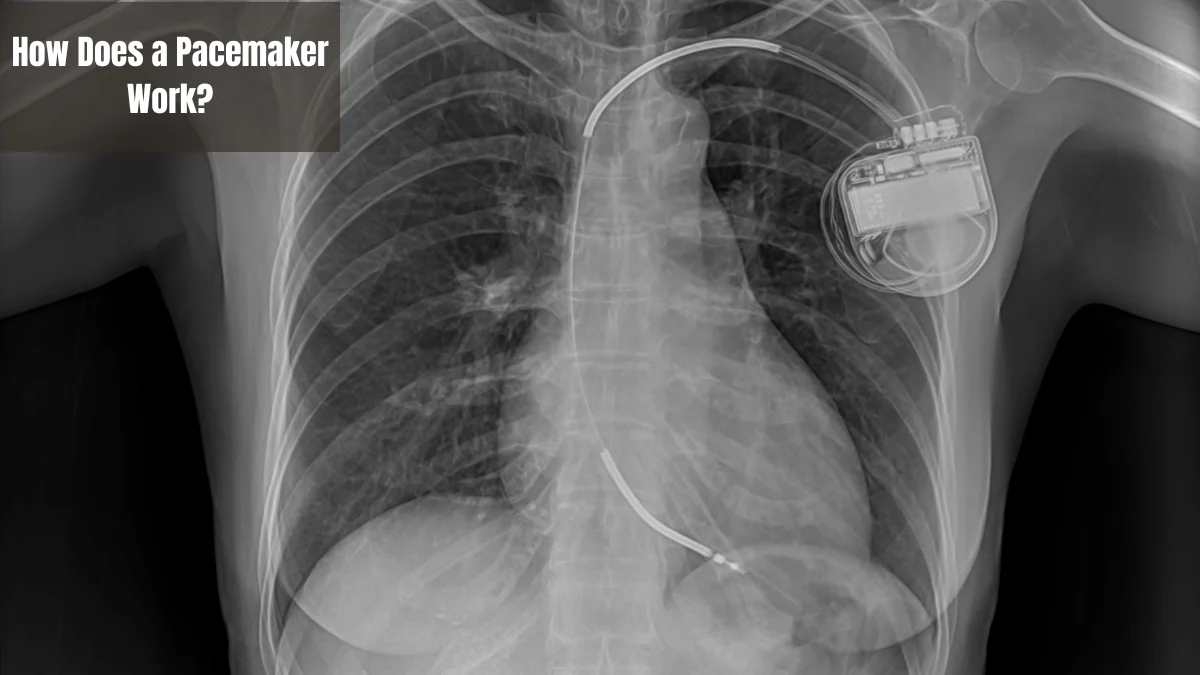

How Does a Pacemaker Work?

The working principle of a pacemaker is to send electrical impulses that replace the natural function of the heart when a disturbance occurs. Here is how it works in detail:

- Heart rate detection: The pacemaker continuously monitors the electrical activity of the heart. If there is an abnormality, such as a slow heart rate, the device can detect it.

- Sending electrical signals: When an irregular heart rhythm is detected, an electrical signal is sent through a lead connected to the heart.

- Heart contraction: The device causes the heart muscle to contract with the electrical signal it sends. This allows the heart to beat normally again.